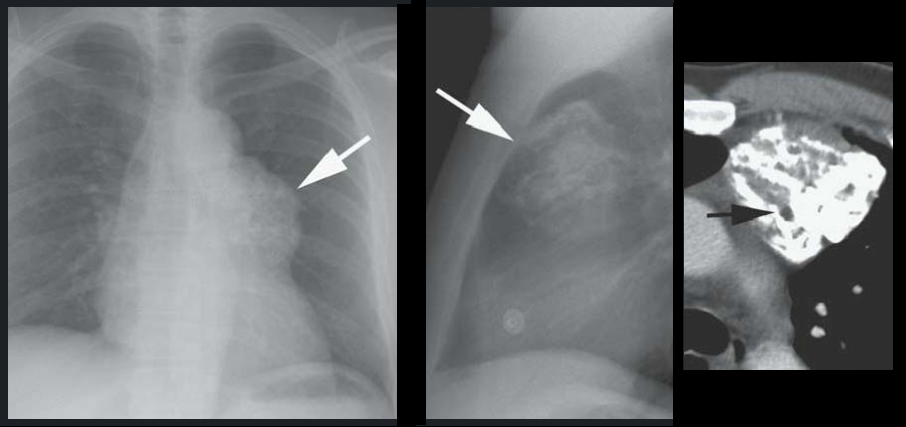

CT

- Bien délimitée

- Graisse

- Kystes

- Calcifications, Dents

- Niveaux hydro-graisseux: très spécifique